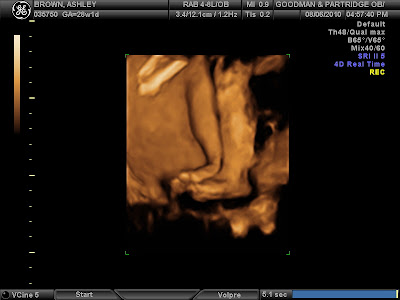

Thursday I will be 7 months and starting the 3rd and final Trimester!!! Time has seriously flown by, but yet has taken soooo long to get here! I’m sooo excited! This Friday we go for our 28week ultrasound and hopefully this will be the last. They are doing one to check growth and fluids, etc. I’m excited to see what our baby will look like from the last ultrasound at 18 weeks to now! I’m soooo excited to meet our son, it’s so insane to think I will be a mom in less than 3 months!!! Breckin is so spoiled already and I love it! haha. I’ve been trying to get things in order with the house as a whole and also his bedroom! We got the crib and I, with my handy wood working skills, put it together! If I may say so myself, it’s turned out quite adorable!

I’ll post pictures from the ultrasound on Friday!!!!